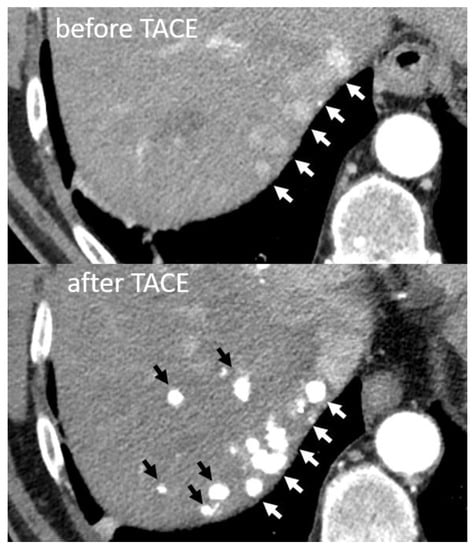

- Nyman Sennefelt, S.; Dimopoulou Creusen, A.; Johnson, U.; Rorsman, F.; Vessby, J.; Ebeling Barbier, C. Peritumoral portal enhancement during transarterial chemoembolization—A potential prognostic factor for patients with hepatocellular carcinoma. Acta Radiol. 2021. [Google Scholar]

- Miyayama, S.; Matsui, O.; Yamashiro, M.; Ryu, Y.; Kaito, K.; Ozaki, K.; Takeda, T.; Yoneda, N.; Notsumata, K.; Toya, D.; et al. Ultraselective transcatheter arterial chemoembolization with a 2-f tip microcatheter for small hepatocellular carcinomas: Relationship between local tumor recurrence and visualization of the portal vein with iodized oil. J. Vasc. Interv. Radiol. 2007, 18, 365–376. [Google Scholar] [CrossRef]